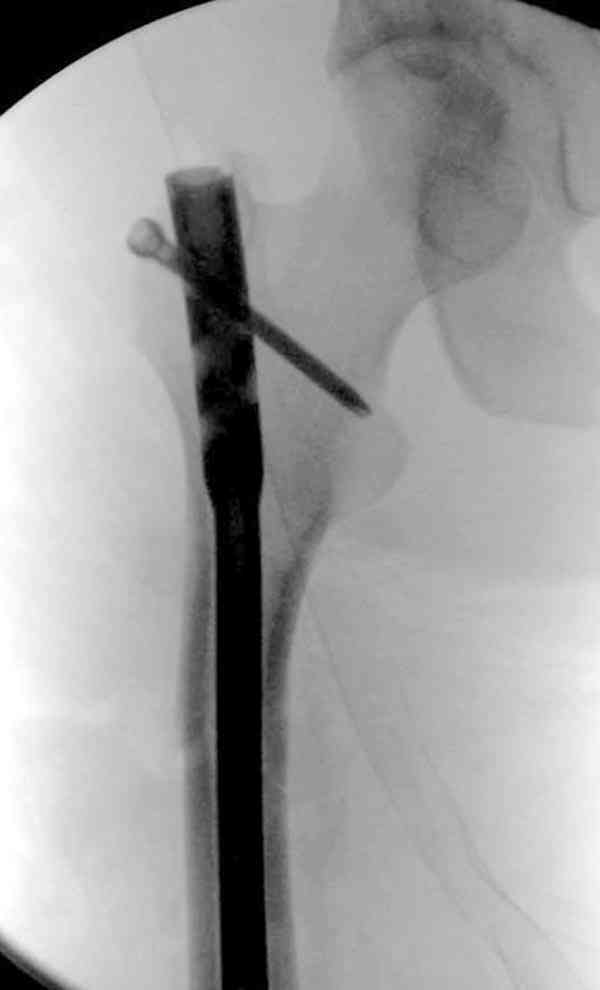

СМ> Что, реально изогнуть титановый гвоздь, не сломав его?

Конечно. Чтобы не сломать, лучше проложить в тиски сразу ниже отверстий полоску металла, чтобы там создалась концентрация напряжений при изгибе, а не на уровне отверстия.

СМ> Если имеются под рукой Р-снимки, продемонстрируйте, плиз.

Вот несколько. С тисками и трубой на днях сделаем.

> Вот несколько. С тисками и трубой на днях сделаем.

Саша, последний штифт, пожалуй, перегнули?

> Саша, последний штифт, пожалуй перегнули?

Там заход сделан как для прямого штифта, не через вертел.